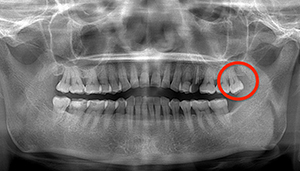

- 抜歯前写真(レントゲン)

| 抜歯内容 | 右下の親知らずは横向きに生えて埋まっているため、麻酔をし親知らずの奥に切開を入れて歯ぐきを開き、歯を囲んでいる骨を削り歯の頭部分を割って出してから、残った根の部分を取り出して抜歯は終了しました。 歯ぐきを切った部分は糸で縫っています。このケースでは根の先端が神経に近く麻痺のリスクがありましたが事前にCTを撮影し、神経との位置関係を確認していたため、麻痺が残ることはありませんでした。 約1週間後に糸取りを行い、その際も多少の痛みや腫れはありましたが後日その痛みも無くなりました。 |